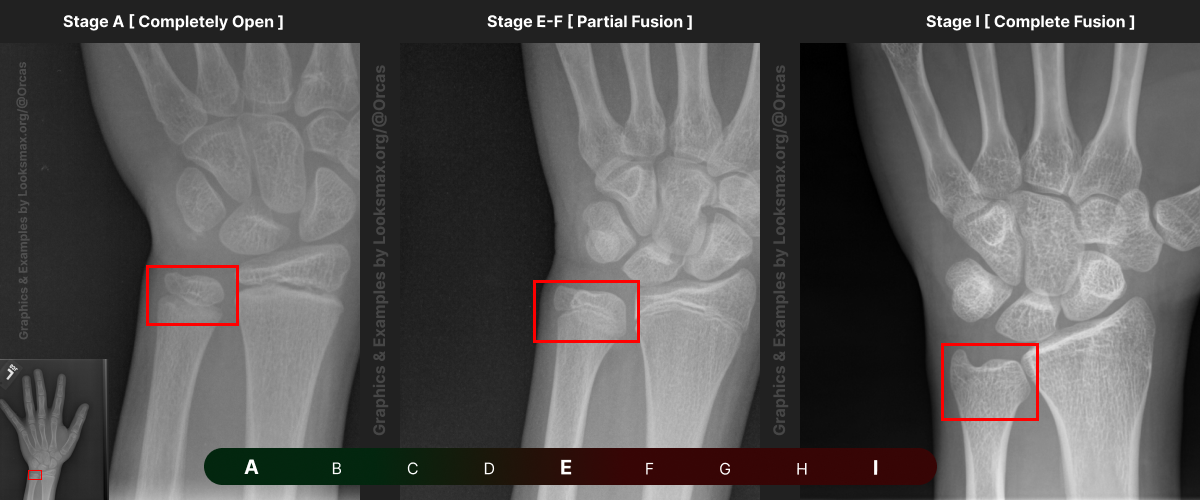

I added references for stages A (Completely unfused), E-F (Partial fusion, basically late stages of puberty), and I (Complete Fusion)

You will have to eyeball this now using your own xrays, I’ve given three examples and some wiggle-room for letters using a reference bar (green-red) below the image, write down your estimated guesses in a text file until you finish all 13 bones.

Don’t doubt yourself, eyeballing isn’t perfect but it still works well, just choose & continue.

“My Radius looks more fused than the image from E-F, but its not as fused as I, it’s closer to the 2nd picture though, so I’ll rate it G” And continue

Bonetype: Radius (distal end)

Check & use the chart below to figure out where you are. Then write your result on a piece of paper or a text file.